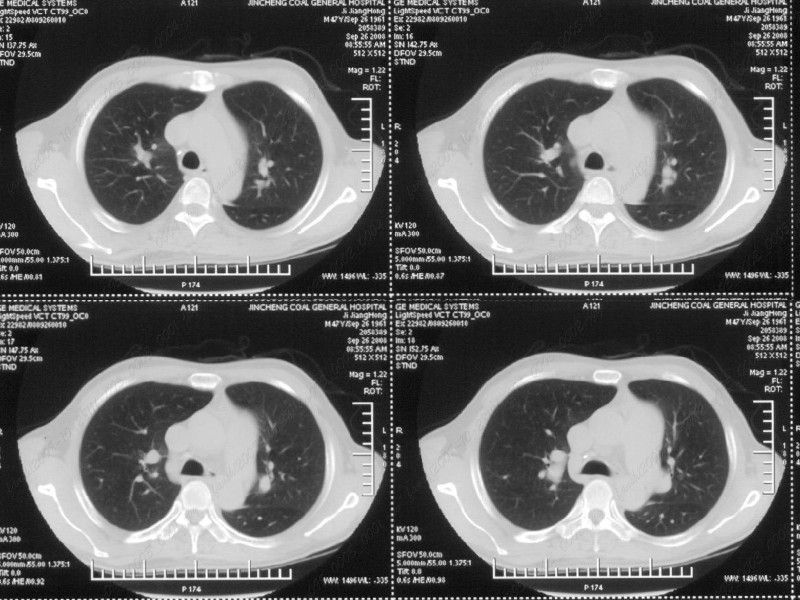

男性,47岁。胸部不适一年,ct检查发现右胸膜下结节。http://www.radida.com/bbs/forum.php?mod=viewthread&tid=46094

病灶周围似有纤维化征像,增强明显强化,但中央可见点状低强化区,考虑慢性病变可能如炎性假瘤等,病灶边缘部分毛糙有切迹,双侧胸腔少量积液影,不除外恶性

结节未见明显强化,局部胸膜增后粘连,内缘纹理影增重伴小围星灶,局部胸膜下小三角状实变影,尖端见纤维索牵扯征,综合考虑炎性病变,有增殖表现,不出外tb灶

汇报临床诊断:右肺动脉分枝栓塞

考虑心脏疾患引起的右侧斜裂增厚。

右肺静脉充盈缺损,左心房体积小,右肺动脉远端动脉充盈缺损,右肺血管影细小,考虑;右肺动脉远端栓塞.

右肺中叶外侧段占位,考虑周围型肺癌伴局限性肺气肿,不除外炎性假瘤